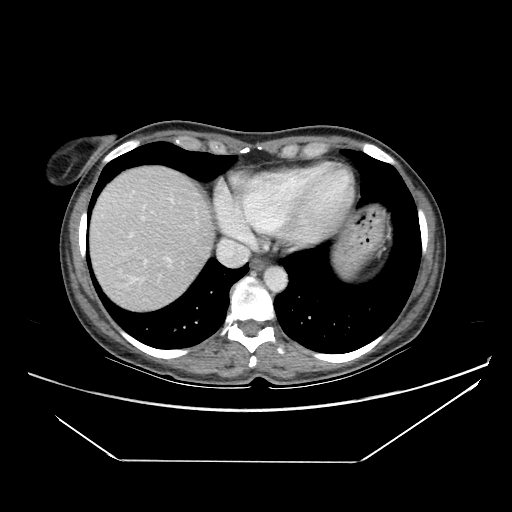

Original VENOUS CT scan

No window - Raw intensity values

Lung window (WL -600, WW 1500 β†’ Low βˆ’1350, High +150)

Mediastinum window (WL 40, WW 400 β†’ Low βˆ’160, High +240)